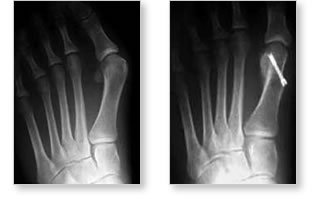

病徵及診斷:

患者拇趾呈外傾及旋轉變形。而第一蹠骨的頭部向內突出。從而發生擠壓、產生發炎。如拇趾外傾嚴重,還會重疊在二趾上或下,影響外觀及令患者疼痛。

臨床檢查後,骨科醫生會為病人照腳部X光片(要病人站著照的方為正確)。正常拇趾外翻角度應少於15度;患上此症拇趾外翻角度則超過15度。此外,醫生還會從X光片,量度其他角度以確定嚴重性並決定診治方法。